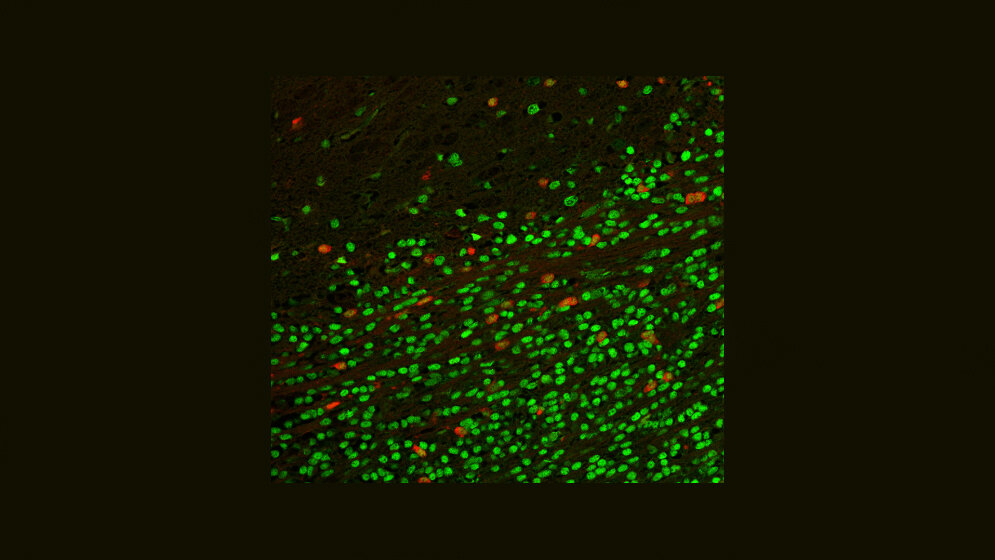

Unter den Proteinen, die in Krebsstammzellen, nicht aber in Gehirnstammzellen gebildet werden, erschien ihnen ein Enzym des Energiestoffwechsels als besonders interessant: Die Glycerol-3-Phosphat Dehydrogenase 1 (GPD1)-produzierenden Krebszellen teilten sich nicht und traten vor allem an der sogenannten Invasionsfront auf, wo der Tumor ins gesunde Gehirngewebe einwächst. Sehr früh, schon etwa zwei Wochen nach dem Beginn der Krebsentstehung, konnten die Forscher im wachsenden Tumor die GPD1-Produktion nachweisen.

Wie schon an den Mäusen beobachtet, fanden sich auch in Gewebeschnitten von Hirntumoren des Menschen die GPD1-produzierenden Zellen vorwiegend an der Invasionsfront. Aus Glioblastomen gezüchtete Zelllinien, deren GPD-1 die Forscher ausgeschaltet hatten, wuchsen in der Kulturschale nicht mehr zu „Minitumoren“ heran – und verloren damit eine typische Stammzell-Fähigkeit.